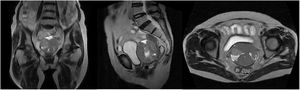

Reporte de casoSe trata de una mujer de 76 años, natural y procedente de la sierra peruana, de raza mestiza, teniendo como antecedente 10 gestaciones que finalizaron en parto vaginal, con fecha de última regla a los 50 años. Presenta un tiempo de enfermedad de 2 años, caracterizado solo por sensación de masa a nivel de hemiabdomen inferior. Es evaluada por el Departamento de Cirugía Oncológica, realizándose resonancia magnética de pelvis: extensa masa sólida quística localizada en el fondo del saco posterior con adecuado plano de clivaje, con un tamaño de 77mm. A los 2 meses es sometida a histerectomía radical, con resultado de anatomía patológica: CAQ de patrón sólido, asociado a carcinoma adenoide basal, tamaño tumoral de 7,5cm, infiltración hasta el tercio profundo de la pared cervical, infiltración perineural ausente, embolia linfovascular ausente, endometrio atrófico, libre de neoplasia en borde quirúrgico, parametrios, ovarios y trompas uterinas. Inmunohistoquímica: CAM5.2, queratina-7, EMA y CD117, positivos, y S-100, negativo.